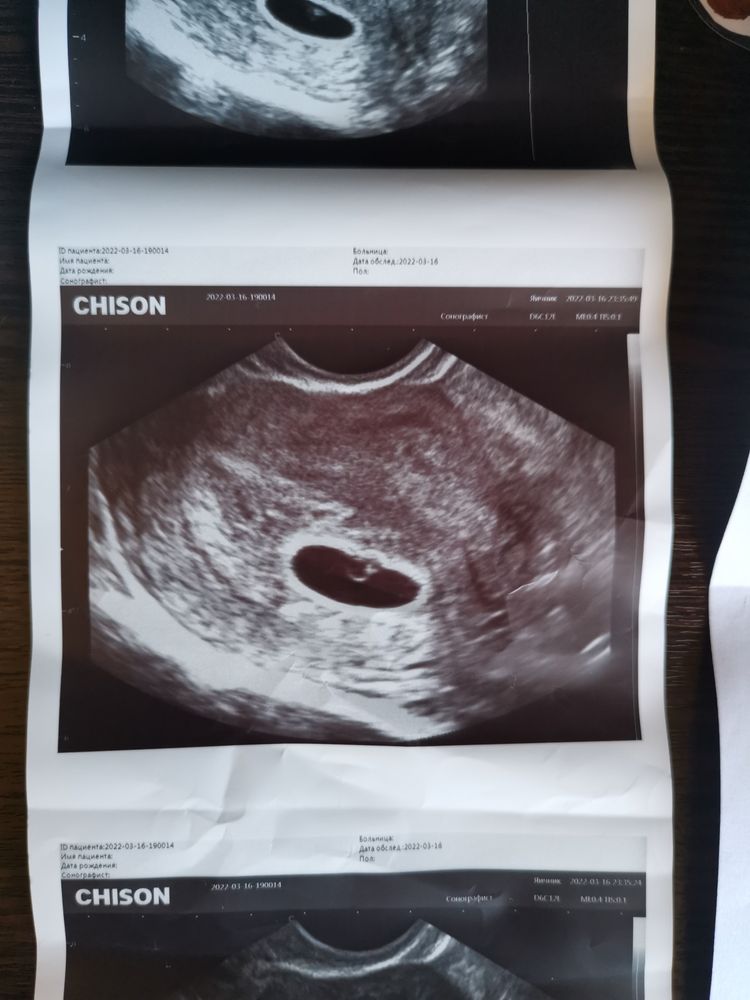

У меня О на 7 дц примерно была, я +7 дней вперед еще к месячным прибавила. Сейчас 9 недель идем по ктр день в день.

Это задержка внутриутробного развития? Замершая?